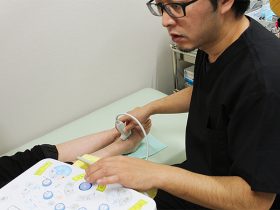

超音波検査(エコー)

近年目覚ましく性能の向上している超音波診断装置を聴診器代わりに用いて診療の様々な場面に役立てています。

レントゲンでは問題がない場合も、さらに一歩進んだ病変の評価や観察が可能となりました。

「ハイドロリリース」「筋膜リリース」(後述)といった比較的新しい治療にも積極的に取り組んできます。

診断

視診や触診、レントゲンだけでは判断しづらい病変の観察が簡便に行えます。

病変部周囲を動かしながら画像評価が行えるのも大きなメリットとなります。

麻酔や各種注射、ブロック治療への応用

目的組織や針先を画面で確認しながら行うため、少量で確実な薬液注入が行える様になりました。その分安全性も向上しました。